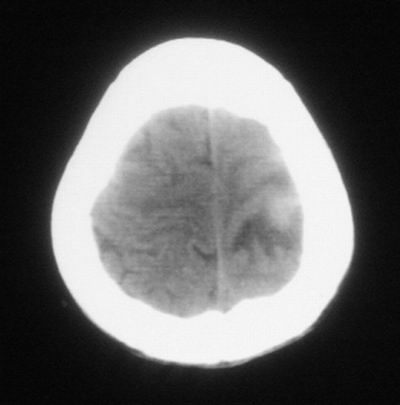

治疗三天后复查ct片示:

治疗三天后复查ct:除左侧额顶叶血肿外。左侧额叶另见片状低密度灶,密度不均匀,境界不清;考虑脑梗塞。